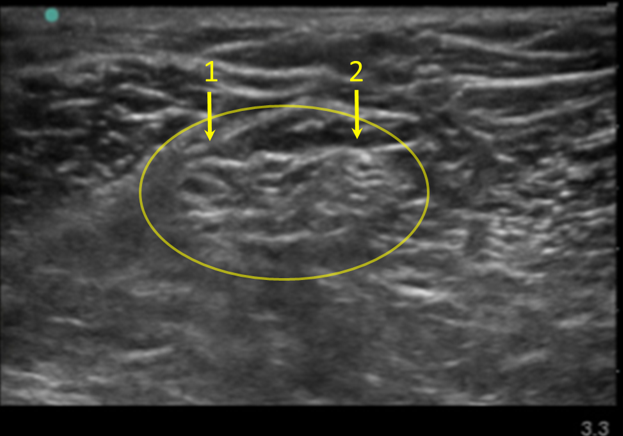

Popliteal Image

Common Peroneal Nerve

Tibial Nerve